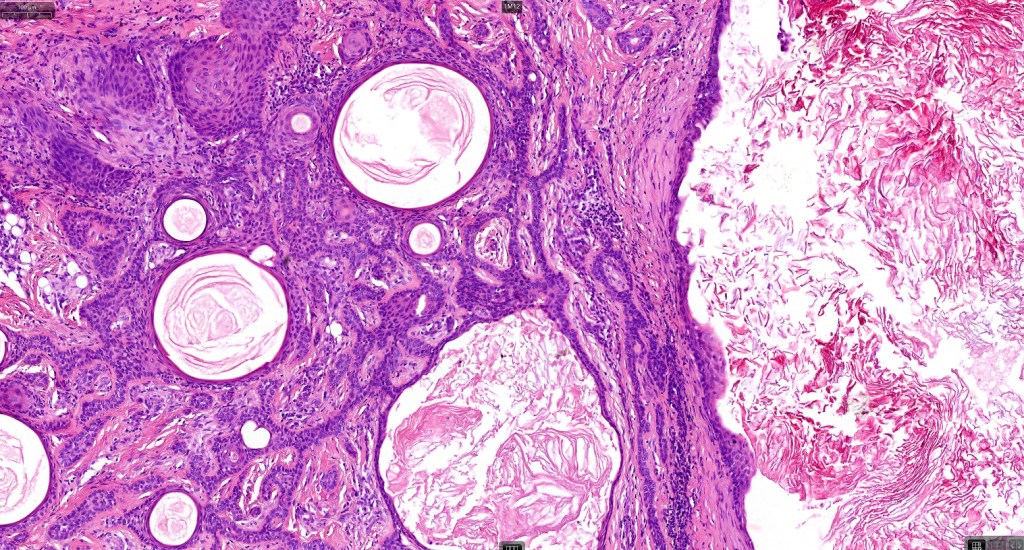

•Well circumscribed unencapsulated, nodular/multinodular silhouette composed of an admixture of epithelial & mesenchymal elements

•Exceptionally matricial change

•Keratocysts & squamous foci

•Stromal sclerosis & hyalinization

•Myxoid change

•Chondroid foci

•Calcification & osteoid